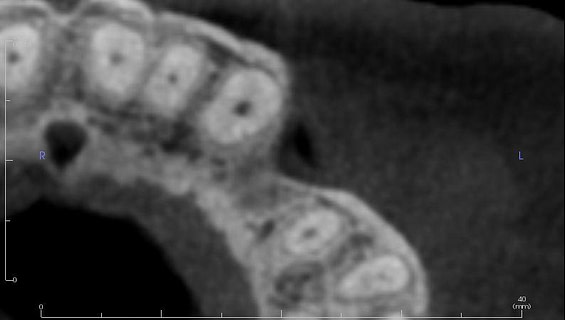

To better understand the patient's overall dental health, a full mouth CBCT scan was taken, confirming the presence of a bony defect in the area where tooth 24 had been surgically extracted.

Pre-surgical planning began with acquiring high-quality diagnostic data, including TRIOS intraoral scans and CBCT imaging. The data was imported into 3Shape Implant Studio, where I designed a virtual crown for tooth 24 and planned the precise positioning of the implant, considering critical factors such as sinus proximity, adjacent roots, bone density, and the location of the bony defect.